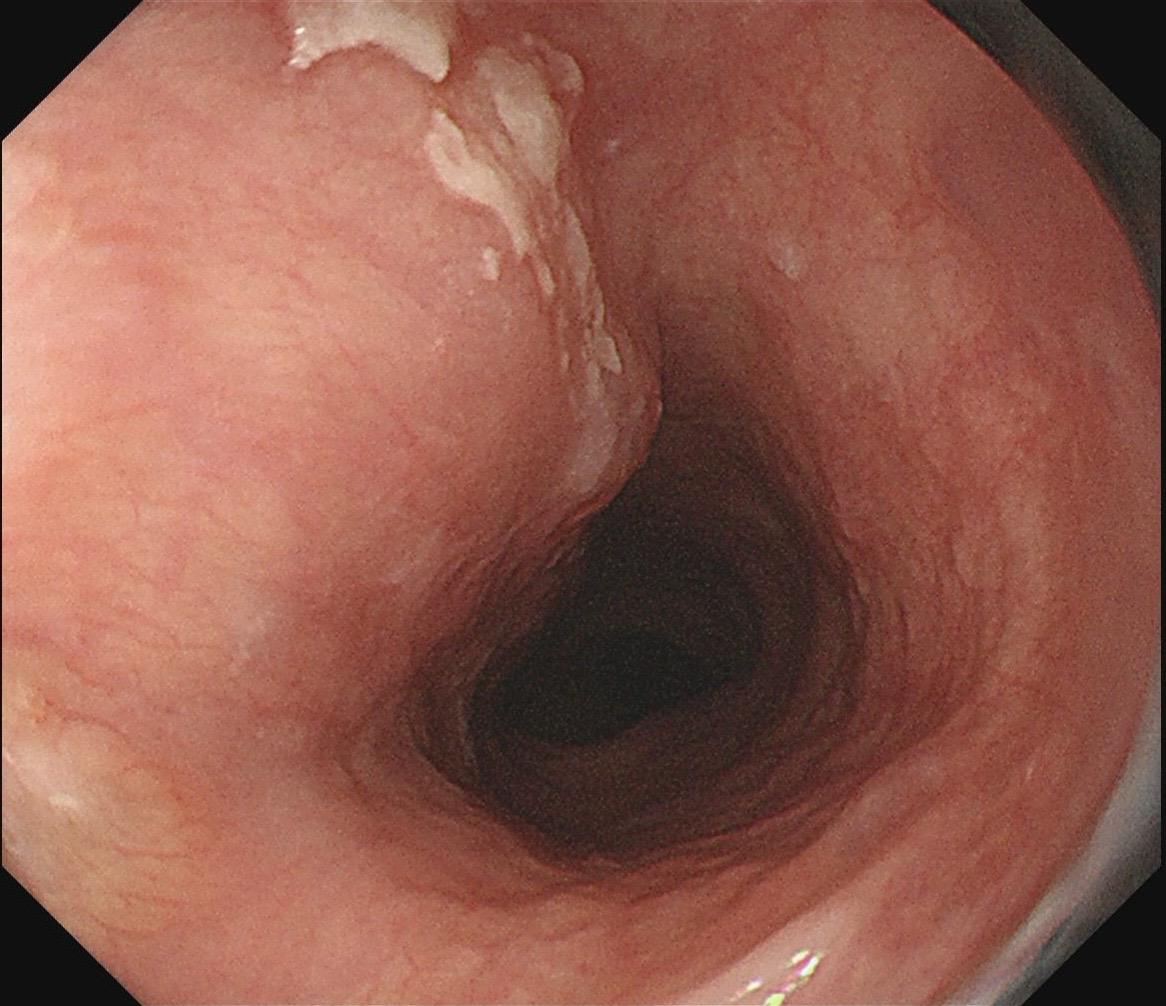

女,73岁,食管双发病变。泰州人,入院系统体检,首次胃镜检查,上段16-19cm见长条状病变,肛侧碘染局部不染;25cm处见一2mm粗糙潮红黏膜,浅凹陷,放大疑似R型不规则血管,卷发样改变,淡染,均行ESD切除。